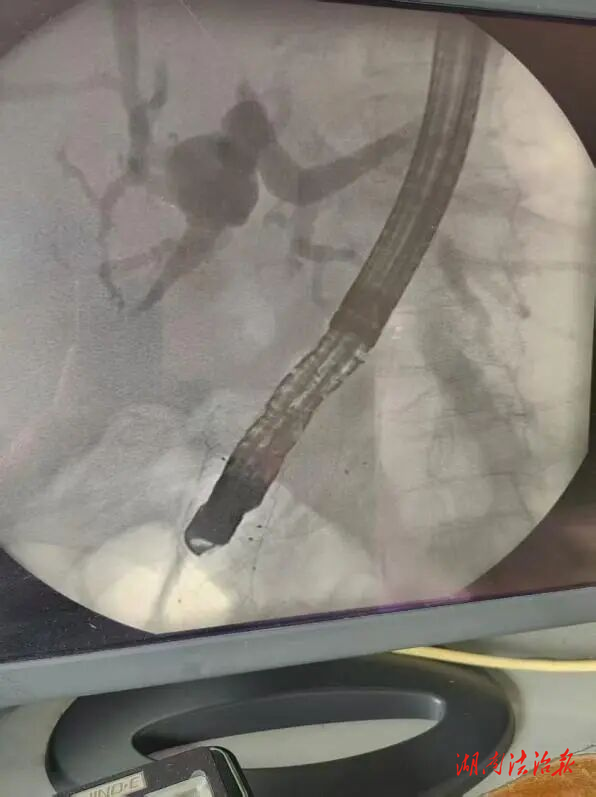

磁共振檢查提示患者膽總管下段軟組織增厚,建議外科PTCD引流術(shù),患者考慮選擇微創(chuàng)治療。消化內(nèi)科組織專家進(jìn)行疑難病例四級(jí)手術(shù)的術(shù)前討論,團(tuán)隊(duì)綜合評(píng)估患者病情與訴求,準(zhǔn)備為其實(shí)施高難度ERCP手術(shù)。術(shù)中需克服十二指腸金屬支架對(duì)十二指腸乳頭的遮擋及腫瘤浸潤(rùn)致乳頭開口等難題,尤其是要對(duì)無(wú)法辨認(rèn)的十二指腸乳頭進(jìn)行膽管插管更是一大難題。手術(shù)成功置入胰管及膽管金屬支架,術(shù)后胰液、膽汁引流通暢,患者無(wú)不良反應(yīng)。